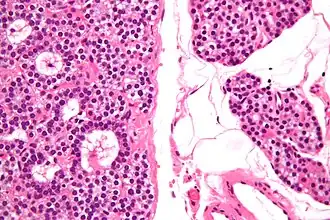

Adénome parathyroïdien en microscopie optique

Un adénome parathyroïdien est une tumeur bénigne des glandes parathyroïdes[1], généralement responsable d'une hyperparathyroïdie primaire par hypersécrétion de parathormone. Le traitement en est chirurgical par parathyroïdectomie.